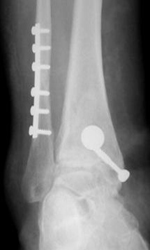

- Artrodesis (fijación articular)

- Prótesis de tobillo.